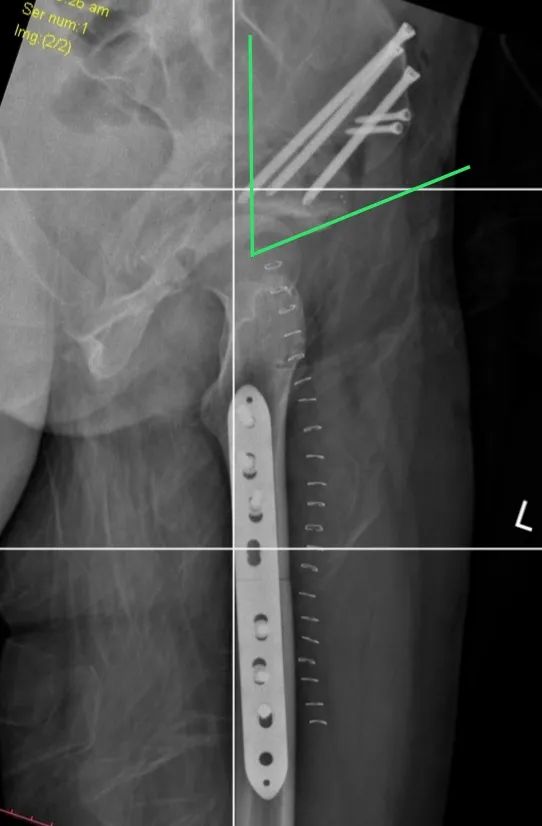

手術(shù)取得圓滿成功,術(shù)后恢復(fù)良好。

術(shù)后

據(jù)了解,髖關(guān)節(jié)發(fā)育不良是引起繼發(fā)性髖關(guān)節(jié)炎的重要致病因素之一,髖臼周圍截骨術(shù)能夠有效改善髖臼覆蓋、增加負(fù)重關(guān)節(jié)面,內(nèi)移髖關(guān)節(jié)的旋轉(zhuǎn)中心,從而減小髖關(guān)節(jié)負(fù)重面軟骨應(yīng)力,達(dá)到預(yù)防和推遲骨關(guān)節(jié)炎發(fā)生的目的。

應(yīng)用髖臼周圍截骨術(shù)治療髖關(guān)節(jié)發(fā)育不良以來,取得了良好的臨床療效,該術(shù)式得到廣泛認(rèn)可與應(yīng)用。